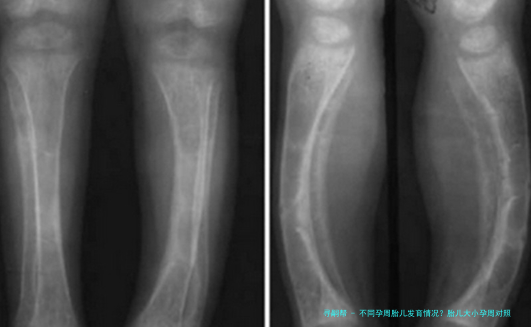

不同孕周胎儿发育情况?胎儿大小孕周对照

自然,每个宝宝的发育节奏不相同,有的快些许,某些慢些许,只要在正常范围内就不必太担心。医生也会通过B超来测量宝宝的双顶部直径、腹部周长、股骨长等指标,综合判断宝宝的成长情形。